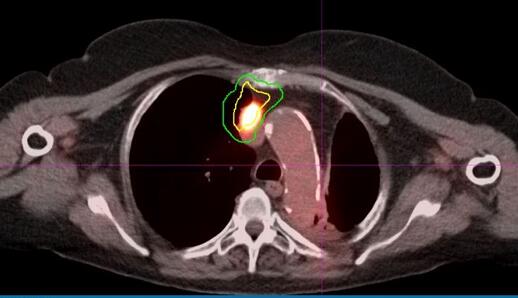

CT引导检是非诊断性的。 手术探查显示,由于纵隔侵袭和出血而无法切除的小细胞癌(图4)。 患者开始用卡铂

图4